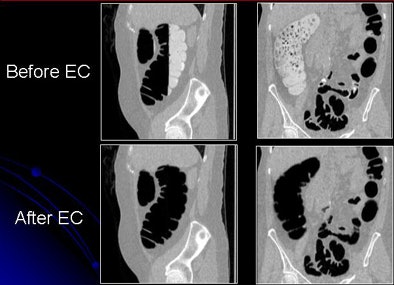

| Images show CTC data before and after electronic cleansing. All images courtesy of Hiro Yoshida, Ph.D. |